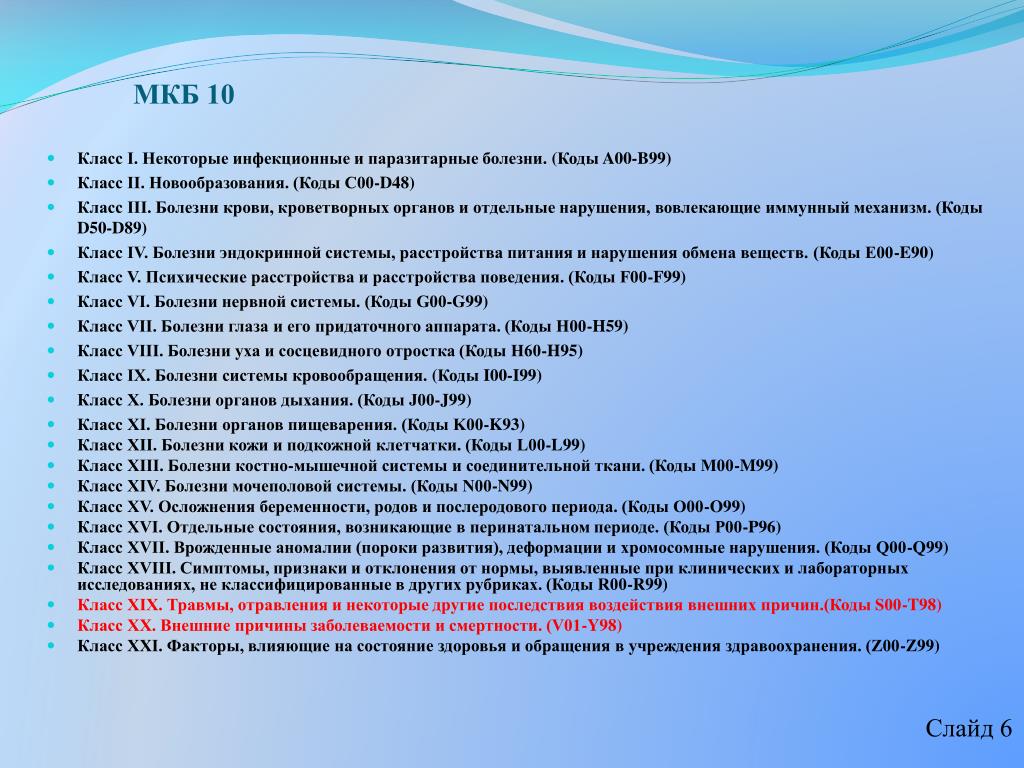

Медицинские изображения и объяснения агенезии почки